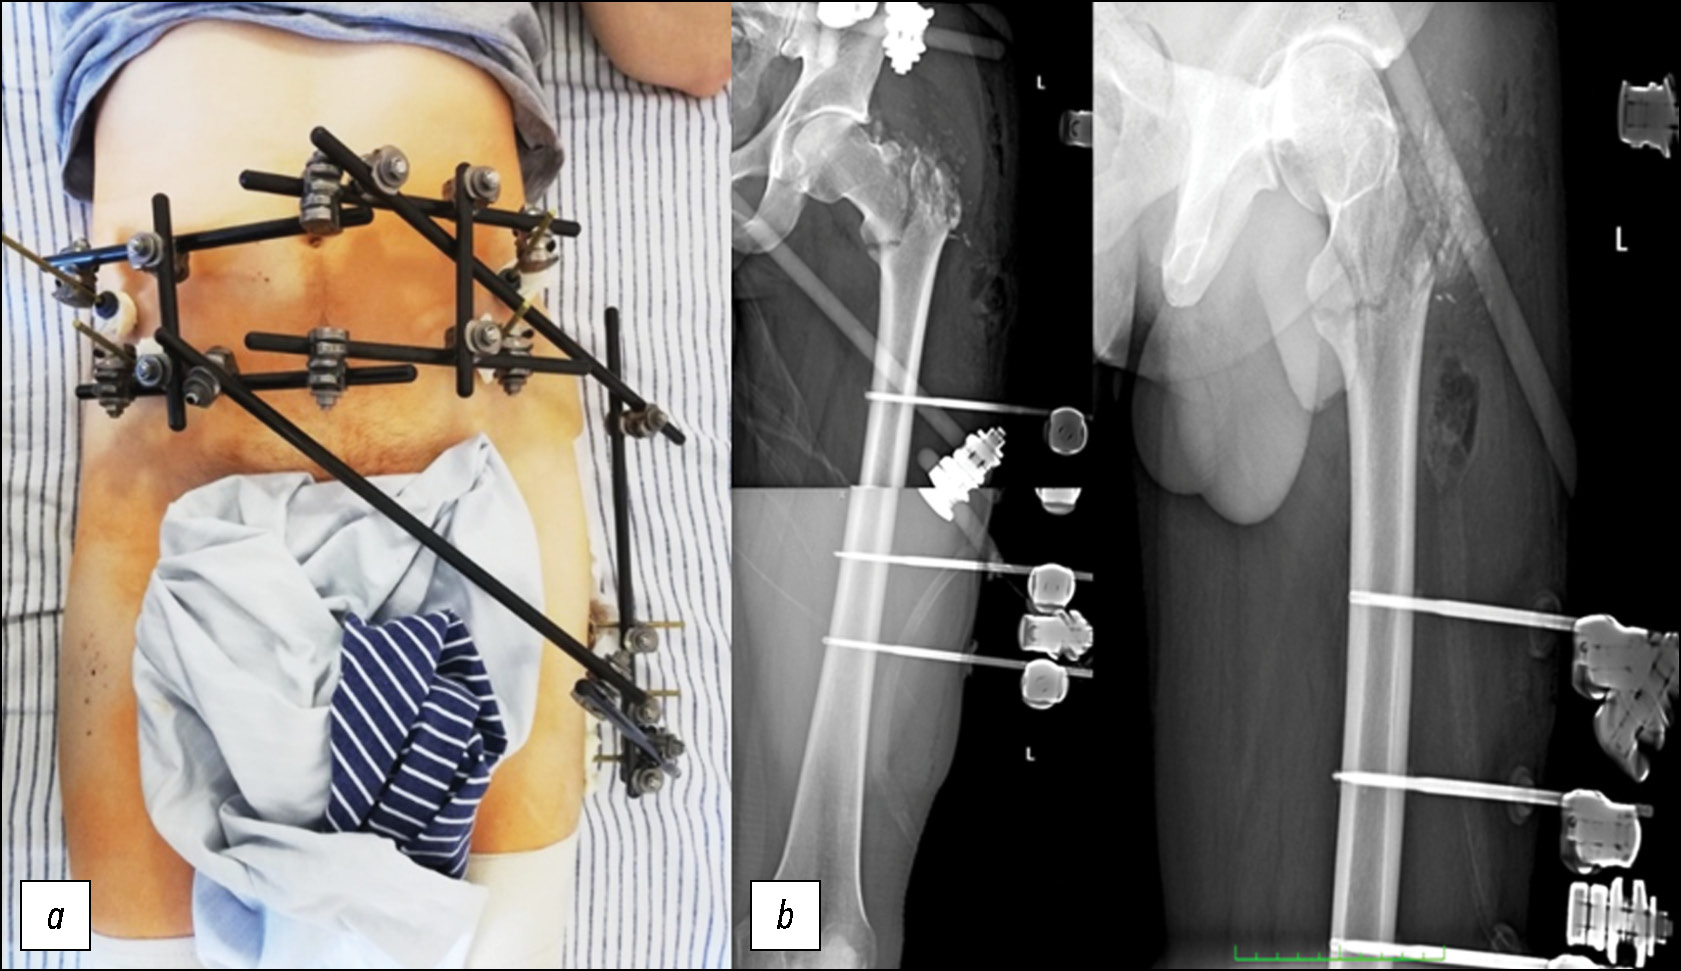

Раненый 36 лет, поступил с диагнозом «осколочное сквозное ранение левой ягодичной области с разрушением большого вертела и чрезвертельным переломом левой бедренной кости со смещением костных отломков» (рис. 3–6).

Рис. 3. Пациент 1: a — внешний вид пациента с наложенным аппаратом внешней фиксации компоновки «таз — бедро» — огнестрельное осколочное сквозное ранение проксимального отдела левой бедренной кости с разрушением большого вертела и чрезвертельным переломом со смещением отломков, b — рентгенограмма после первого этапа — стабилизация повреждённой конечности в аппарате внешней фиксации.

Fig. 3. Patient 1: a, the patient with an external fixation device in a “pelvis–femur” configuration; through-and-through shrapnel wound of the proximal left femur with destruction of the greater trochanter and a displaced intertrochanteric fracture; b, radiograph after the first stage: stabilization of the injured limb using external fixation.